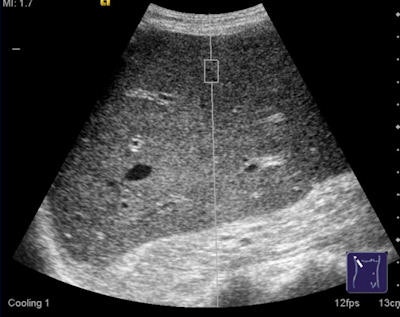

An ARFI examination can be performed on patients with ascites and those in whom liver stiffness measurement by transient elastography could not be obtained. Image courtesy of Dr. Ioan Sporea.David Zizka is a communications specialist in the European Society of Radiology's (ESR) press office.

The technique uses high-energy, focused acoustic pulses and conventional diagnostic sonography methods to measure tissue elasticity. An acoustic "push" pulse is produced by the ultrasound probe and generates shear waves that are propagated into the liver. Using image-based localization and proprietary implementation of ARFI technology, shear-wave speed may be quantified and, in precise anatomical regions, focused on a region of interest, with a predefined size provided by the system.

The force impulse causes displacement of the tissue, and the time scale of this response is much slower than that of the acoustic propagation. The interaction of sound with tissue can be used to receive additional information about the diagnosed region, beyond what is normally provided in an ultrasound image. The velocity is proportional to the tissue stiffness, with faster wave progression occurring through stiffer material, and is measured in meters per second, Sporea stated.